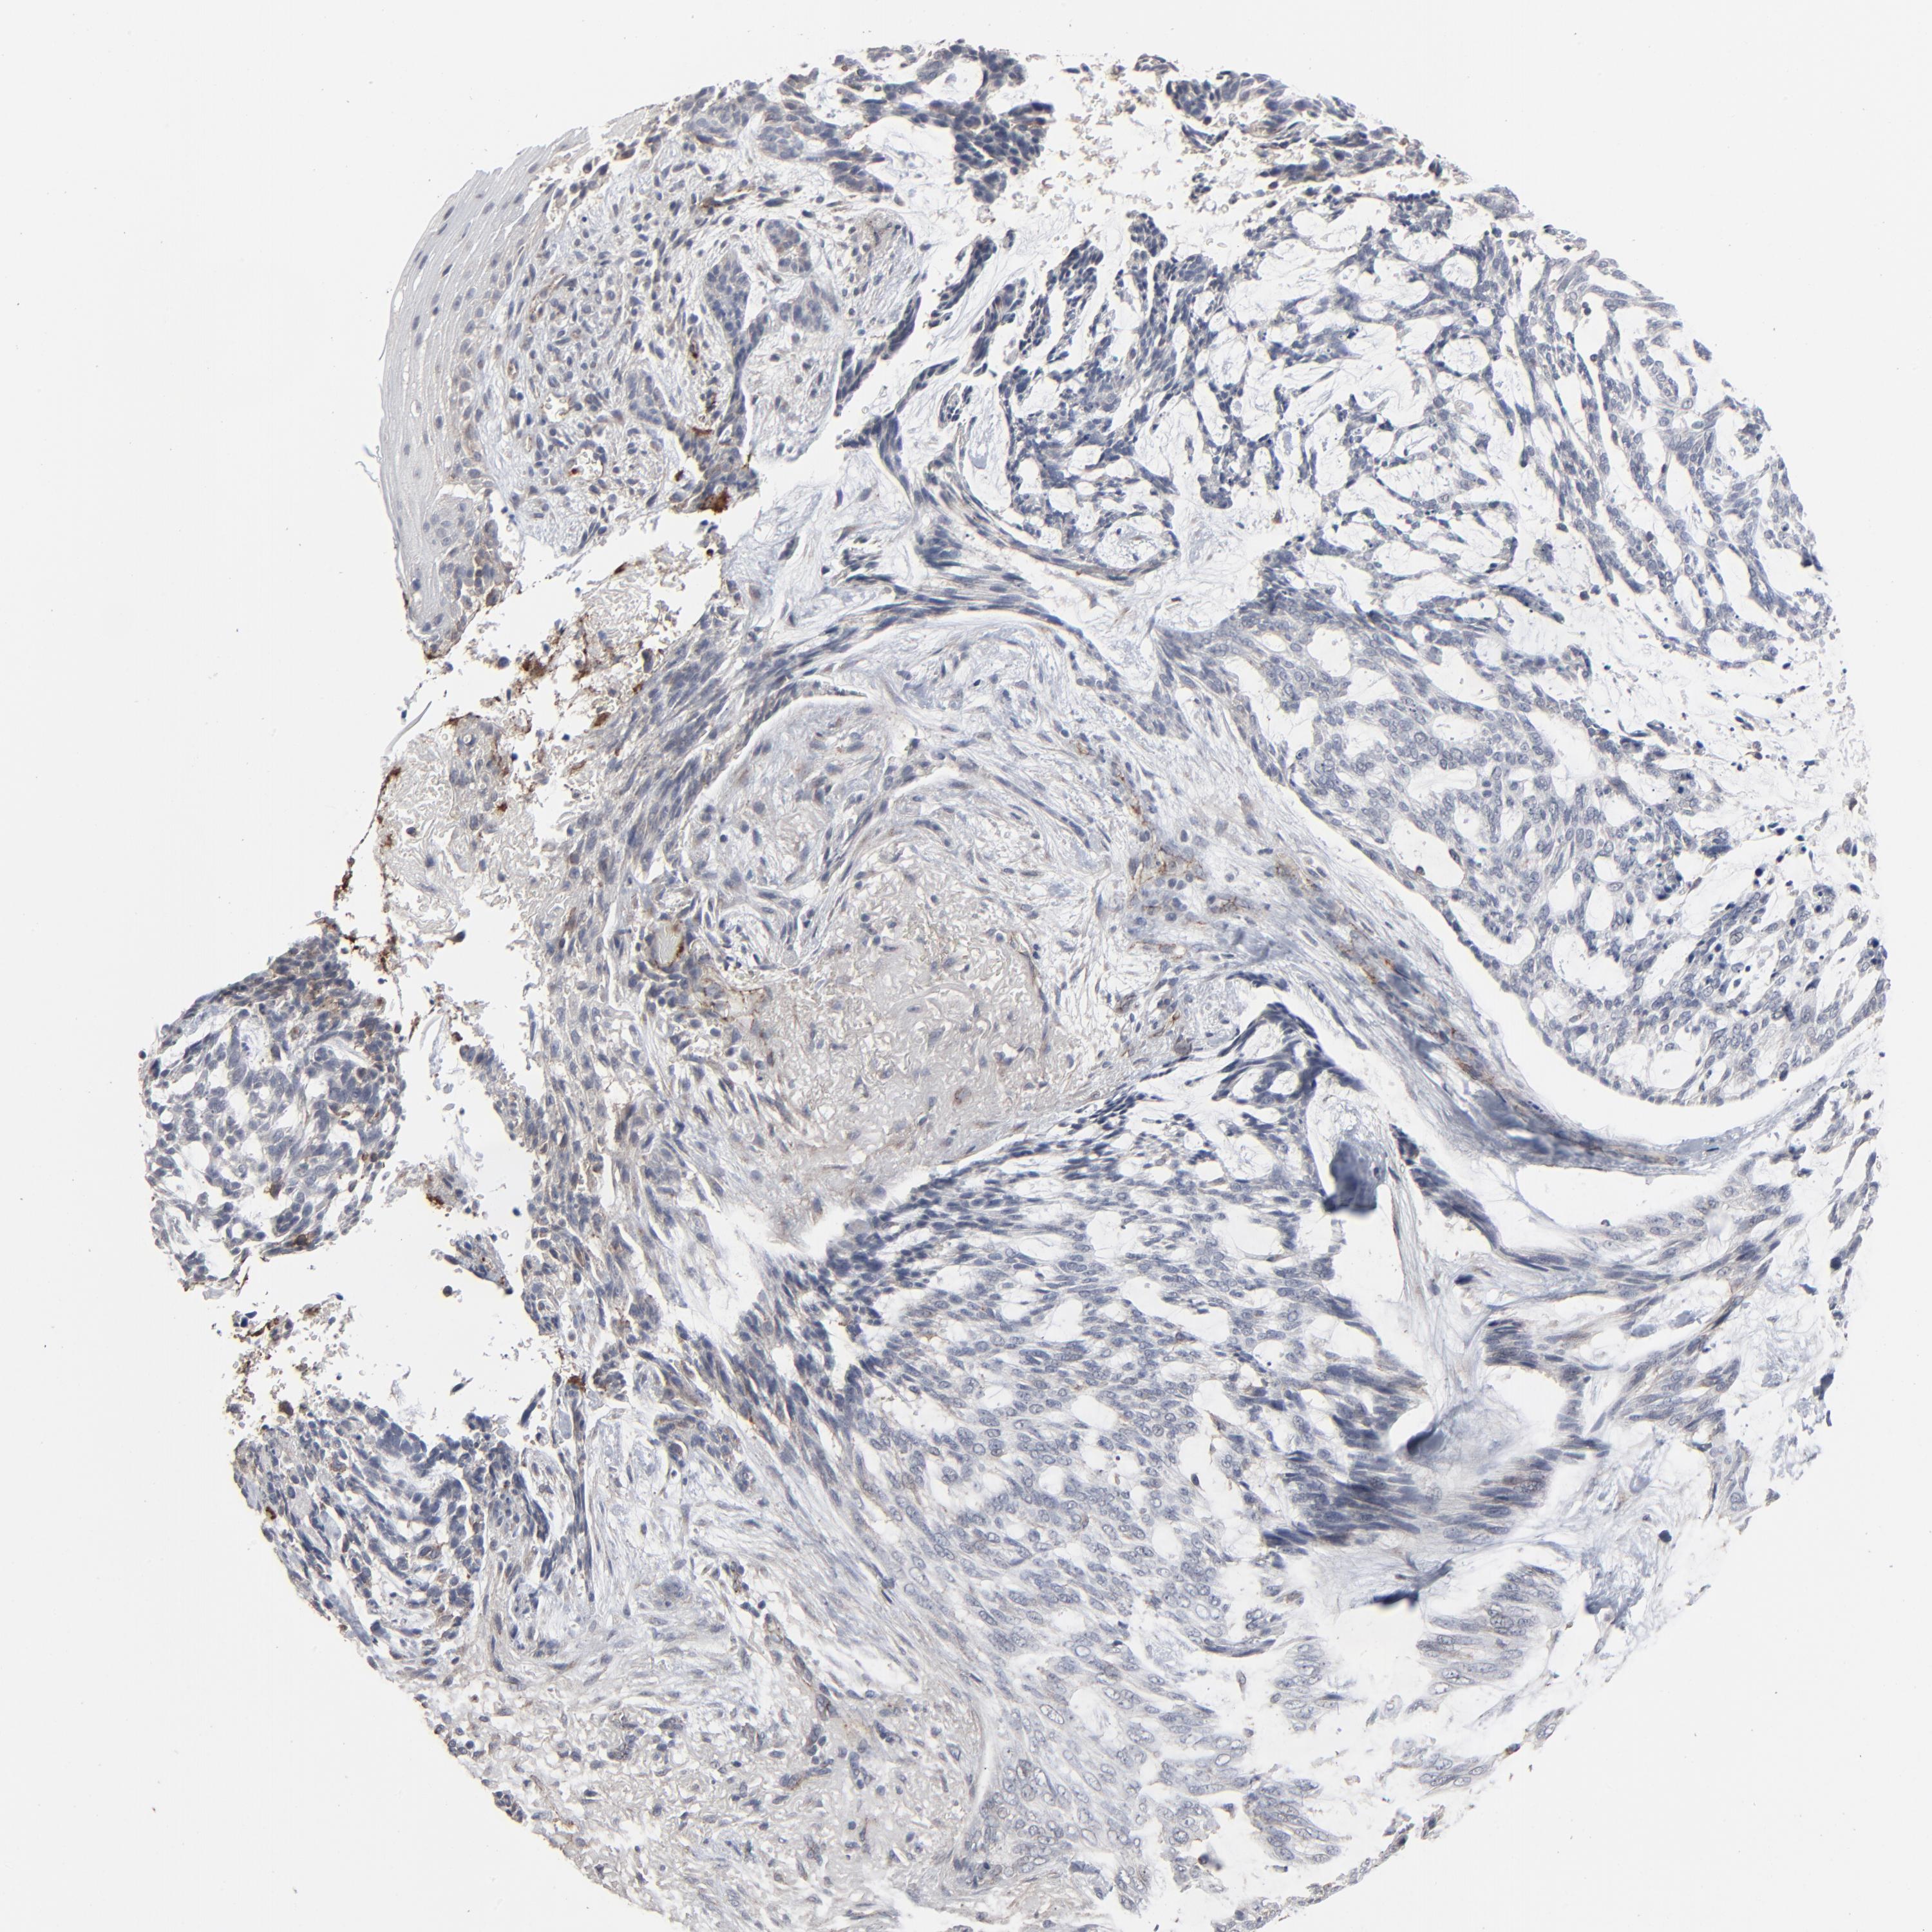

SKIN CANCER - Protein expressioni

A mouse-over function shows sample information and annotation data. Click on an image to view it in a full screen mode. Samples can be filtered based on level of antibody staining by selecting one or several of the following categories: high, medium, low and not detected. The assay and annotation is described here.

Antibody stainingi

Antibody staining in the annotated cell types in the current human tissue is reported as not detected, low, medium, or high, based on conventional immunohistochemistry profiling in selected tissues. This score is based on the combination of the staining intensity and fraction of stained cells.

Each image is clickable and will lead to virtual microscopy that enables deeper exploration of all samples and also displays staining intensity scores, fraction scores and subcellular localization as well as patient and tissue information for each sample.

Antibody HPA003417

Staining

High

Medium

Low

Not detected

Intensity

Strong

Moderate

Weak

Negative

Quantity

>75%

75%-25%

<25%

None

Location

Nuclear

Cytoplasmic/membranous

Cytoplasmic/membranous,nuclear

Basal cell carcinoma